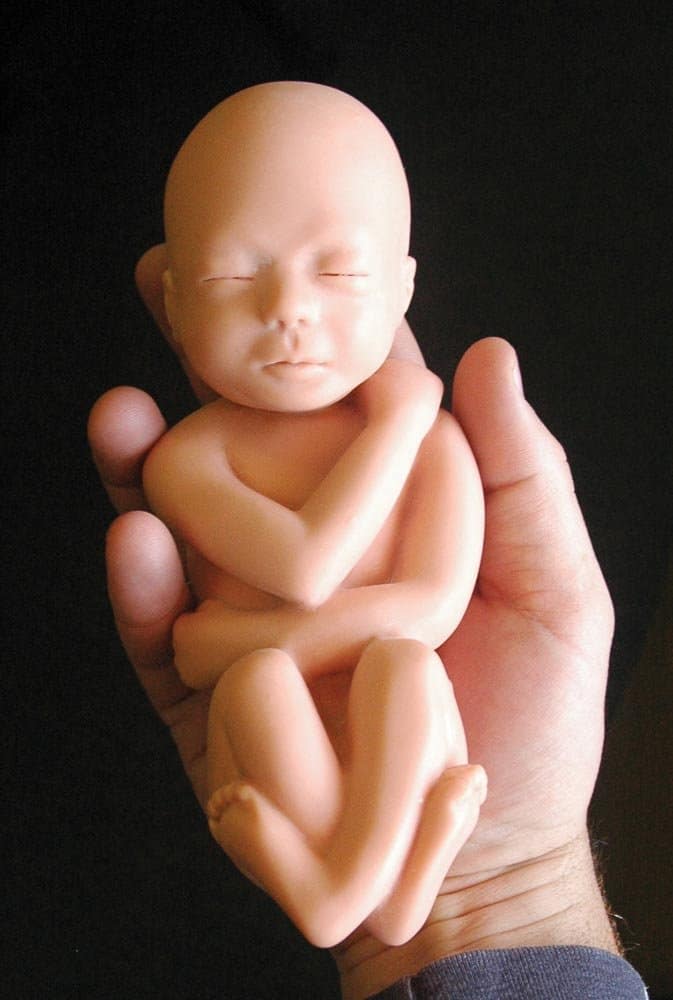

Раздел: Снимки-откровения